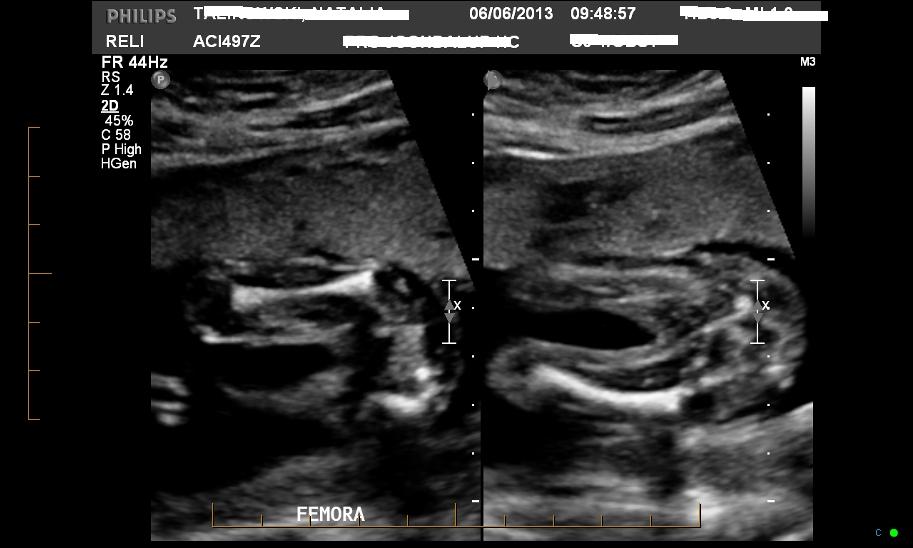

Another shot

Looks like a girl to me as I see no 'boy parts' :)

MAYBE girl....only because I can't see any obvious boy bits...but they could be hiding...